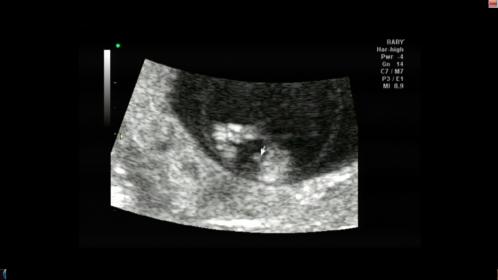

It is totally 50/50 this early so I'd keep any and all hope you have at this point! Good luck :)

no clues in this hope you get your desired gender

Not enough clues just yet hunny - but I feel like you're having a girl! :o

Still too early i think, hang in there :)

It is too early.. Can go either way.. Hope the (healthy) pink way!